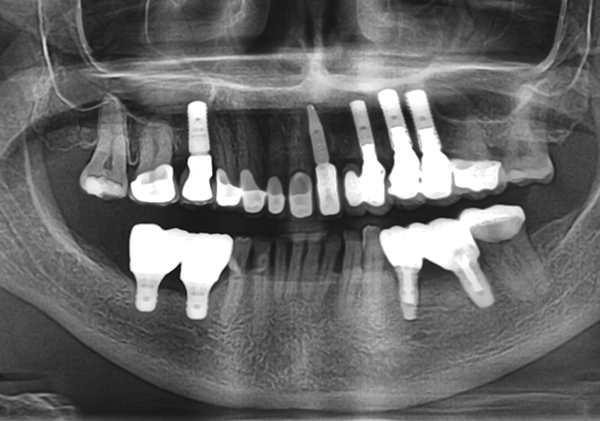

Straumann blt xray. Prophylaxis paste and cup 4. Bone level tapered implants blt refine. Implant blt the straumann bone level tapered implant comes in the materials roxolid with the slactive and sla surface or titanium with an sla surface a unified color code simplifies identification of instruments and im. X ray holder and film 2.

O 29 mm 1 o 33 mm 2 o 41 mm 2 o 48 mm. Straumannbone level tapered blt soft bone hard bone mandible in densifying mode make sure your osteotomy is 10 mm deeper than the actual implant final length. The straumann bone level tapered blt implant offers all the clinically proven features of the straumann bone level implant line plus the advantages of a tapered implant body. Implant blt straumann dental implant system.

In extreme hard bone utilize dac densify after cut protocol. Tissue level implants bone level implants. The shape surface and material combination are designed to deliver primary stability in all bone classes making the straumann bone level implant ideal for. Disposable saliva ejector and control pads 5.